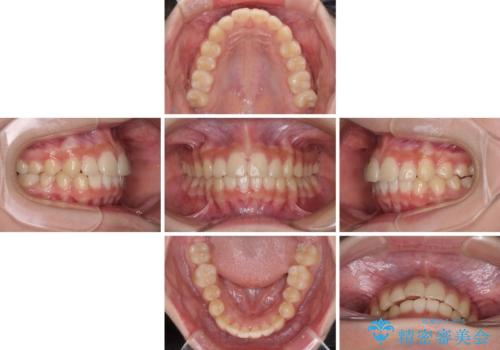

下の前歯が隠れてしまうほど深い咬み合わせ 高校生のインビザライン矯正治療

- 前歯の叢生と深い咬み合わせを気にして来院された患者様です。

奥歯の咬み合わせを見ると、上顎が下顎に対して相対的に前方にありました。

深い咬み合わせを改善するためには、上顎臼歯を後方に移動させつつ、下顎の小臼歯を直立させる必要があります。

インビザライン単体で対応ることも検討できますが、達成する可能性が低いため、カリエールディスタライザーという補助装置を併用して、より確実性を上げることとしました。

奥歯の咬み合わせと深い咬み合わせを改善した後、インビザラインで歯列を整えることとしました。

ワイヤー装置と補助装置を有効に活用し、さらには高校生ということもあり、1年9か月で狙い通りの仕上がりを達成することができました。